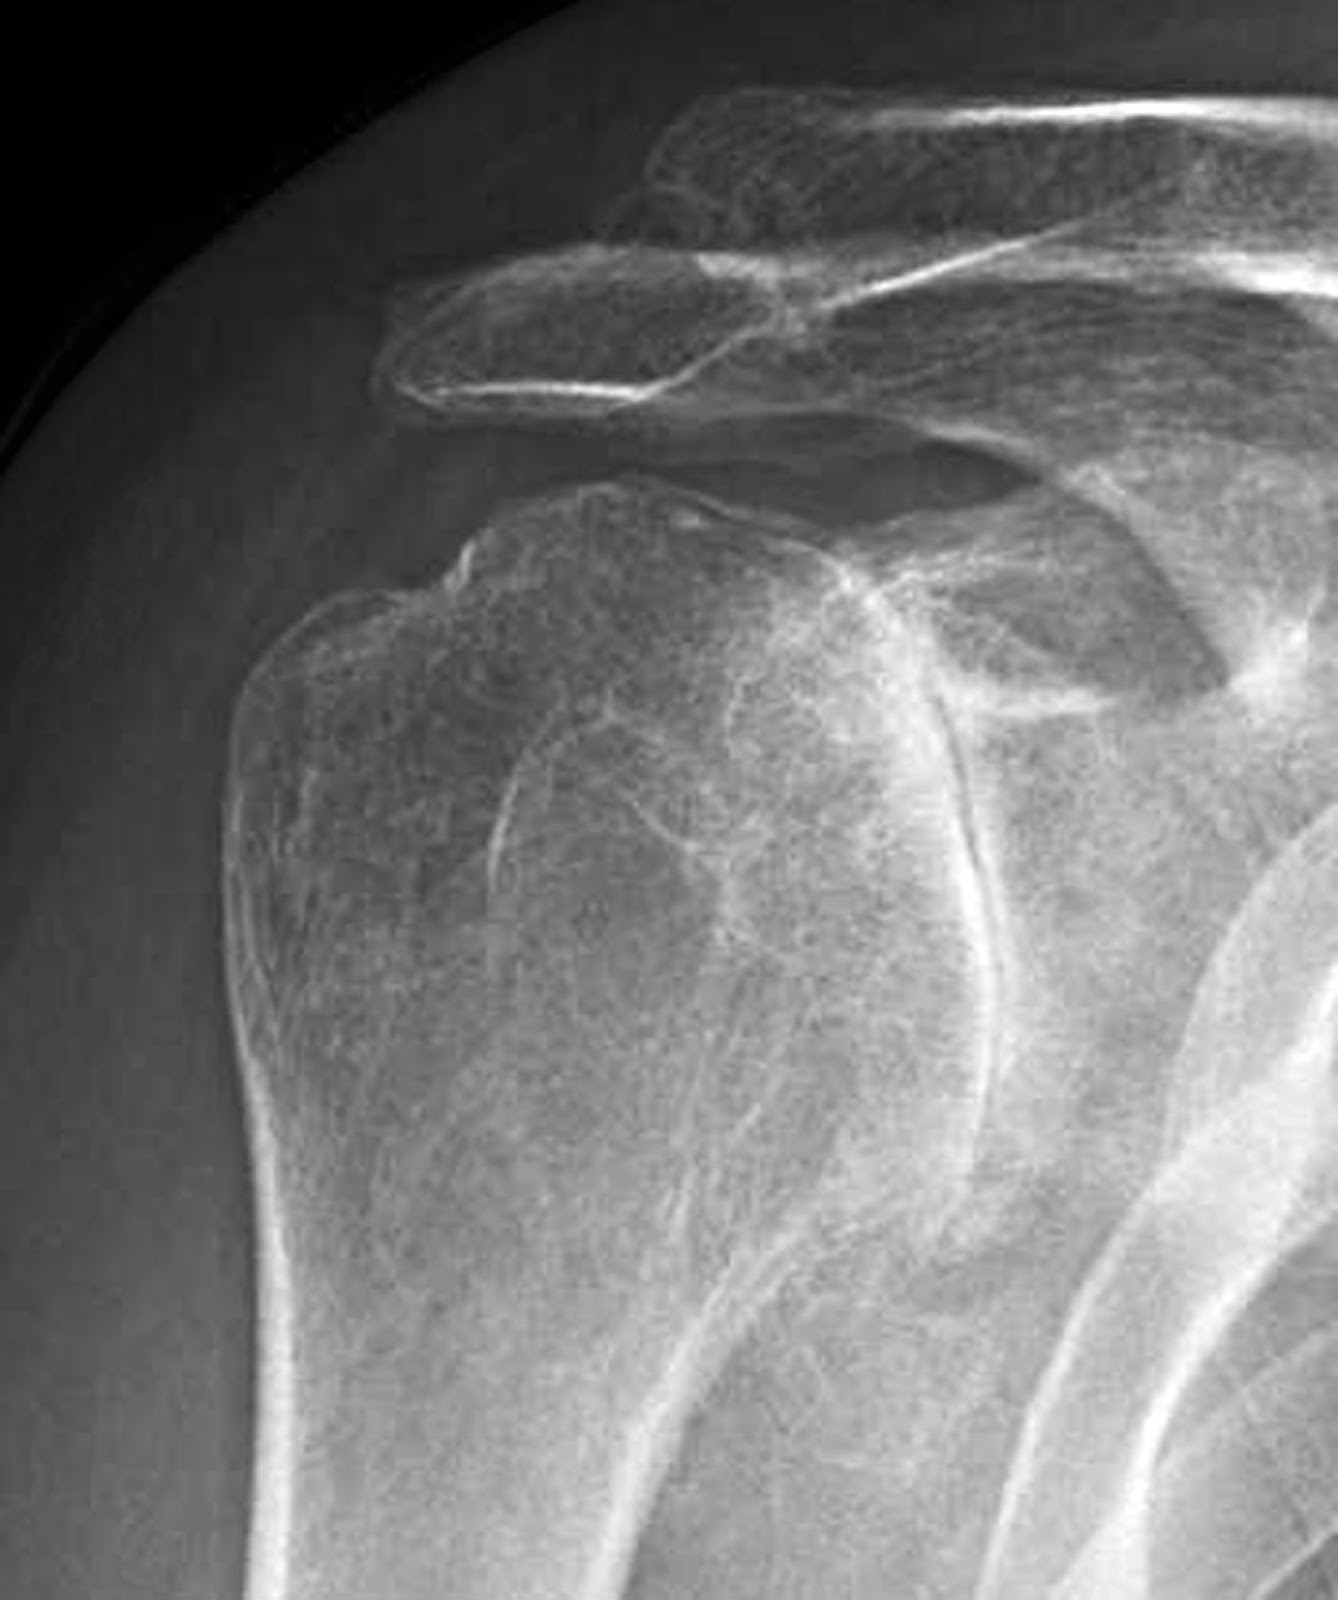

Acromioclavicular (AC) Joint Arthritis What to Know

Acromioclavicular Joint Arthritis Sydney Shoulder Unit Inflammatory Arthritis In Shoulder In an arthritic shoulder, inflammation causes pain and stiffness. Shoulder osteoarthritis can be a painful and debilitating disorder. Simply defined, arthritis is inflammation of a joint. The inflammation affects the lining of the joint capsule,. Friction in the joint increases, pain increases and you slowly lose mobility and function. Rheumatoid arthritis is a type of inflammatory arthritis which typically starts. Inflammatory Arthritis In Shoulder.

Acromioclavicular (AC) Joint Arthritis What to Know Inflammatory Arthritis In Shoulder What is osteoarthritis of the shoulder? The shoulder joint is the third most common joint in your body that osteoarthritis affects, behind knees and hips. Symptoms of shoulder arthritis may include pain in the shoulder joint, stiffness and reduced range of motion. Friction in the joint increases, pain increases and you slowly lose mobility and function. Simply defined, arthritis is. Inflammatory Arthritis In Shoulder.